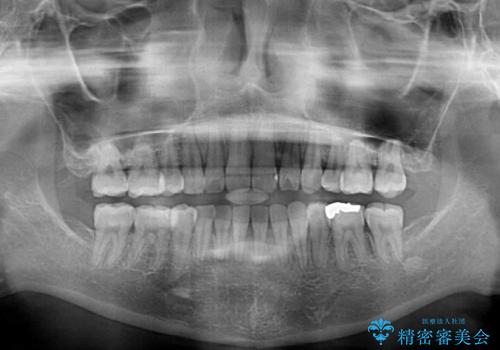

舌の突出癖の影響もあり、非抜歯矯正で治療開始したものの口元が突出し、唇が閉じにくくなってしまったため、途中で第一小臼歯4本を抜歯ししました。

口元の突出感のない、すっきりとした仕上がりとなりました。